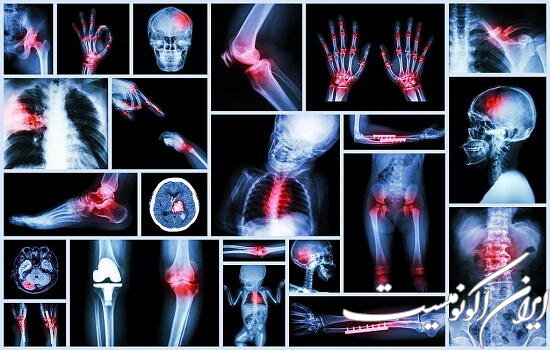

کارگاه «تفسیر انواع گرافی در پرستاری» برگزار می‌شود

انجمن علمی دانشجویی پرستاری دانشگاه آزاد اسلامی واحد اصفهان خوراسگان، کارگاه تفسیر انواع گرافی در پرستاری را برگزار می‌کند.

به گزارش باشگاه دانشجویان ایران اکونومیست، این کارگاه پنجشنبه ۱۱ اسفندماه، ساعت ۱۴ الی ۱۸، با تدریس دکتر رحمتی ـ رئیس بیمارستان خمینی شهر،  به‌صورت حضوری در دانشکده پرستاری مامایی دانشگاه آزاد اسلامی واحد اصفهان خوراسگان، به تفسیر مقدماتی و پیشرفته MRI. CXR.ctsoan،  می‌پردازد.